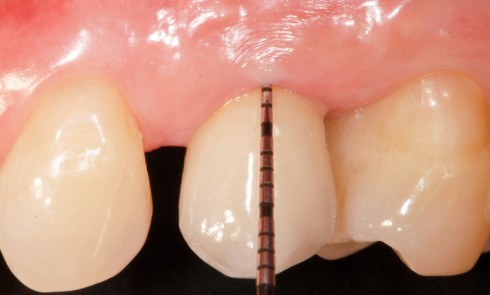

Article réservé à nos abonnés Traitement d’une péri-implantite par chirurgie de régénération osseuse guidée

La patiente 61 ans Sous bêta-bloquant Bonne hygiène orale Parodontite traitée et stabilisée depuis 2016 Maintenances tous les 6 mois...